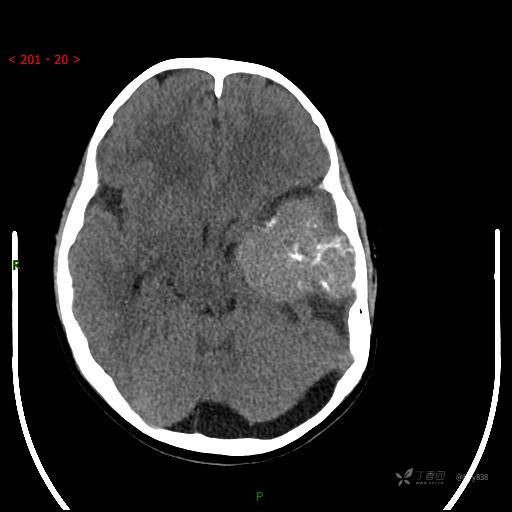

“典藏”病例分享。10岁儿童,头痛头晕一周余,CT、MRI 都有---结果公布~

简要病史:患者于一周前无明显诱因开始出现头痛头晕,无恶心呕吐,无肢体抽搐,无寒颤高热,无腹胀腹泻,无视力下降及视野缺损,上述症状休息后可稍缓解,未引起重视。 2天前患者头痛头晕不适加重,伴有恶心感,无呕吐,遂到当地人民医院行头颅CT检查示:左侧颞部占位性病变,今日家属为求进一步治疗,来我院门诊求治。门诊拟“左侧颞部占位性病变”收入我科。 患病以来,患者精神、饮食、睡眠尚欠佳,大小便如常,体力体重无明显变化。

临床诊断:左侧颞部占位

颅脑CT扫描